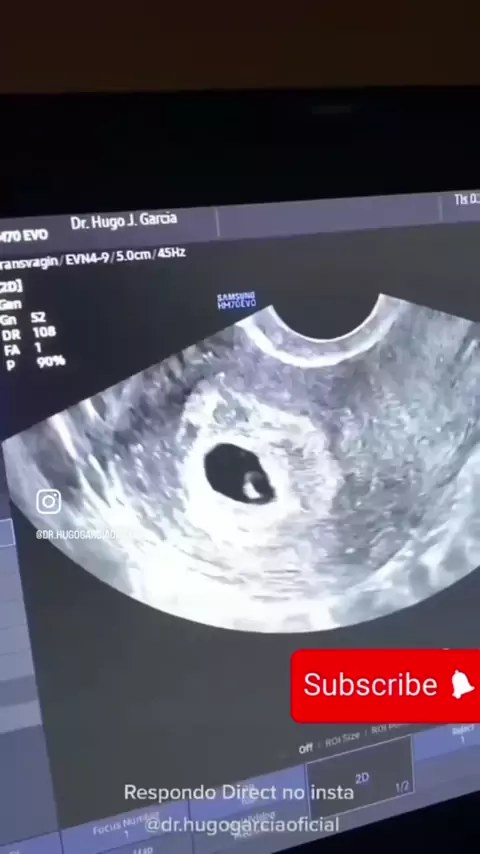

Dr.hugogarciaoficial